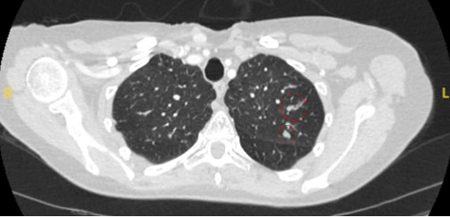

Computed tomography (CT) showing two areas (red circles) of mucoid impaction of the left upper lobe subsegmental bronchi, resulting in appearance that mimics a nodule

From the collection of Dr George Tsaknis, MD, PhD, FRCP(London), MRQA, MAcadMEd, PGCert; used with permission